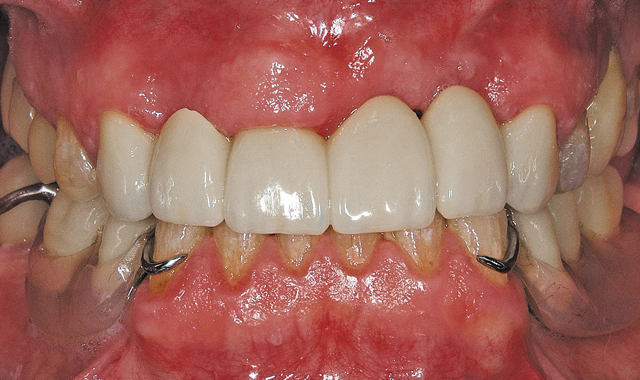

Fig. 8 Bucal view CO: Final bridge from Connect Case

12 Now we have a display of the actual finished case. I can now simply export the file to the inLab MC X5 wet/dry milling unit, and it’s ready for milling. The final product was milled with zirconia and then shipped it back to Chile. Both patient and doctor were extremely pleased with the results (Fig. 15).

Fortunately, a case I can share with you is another one I worked on with Dr. Ilic. He helped me to efficiently and safely navigate the delivery process to Chile and then sent me a case via Sirona Connect for a full zirconia six-unit biocopy that he scanned with his CEREC Omnicam. All the way from Chile, I was able to partner with Dr. Ilic on a fantastic model-less case that I was able to create and mill using the new inLab SW 15 and the inLab MC X5 wet/dry milling unit, respectively.